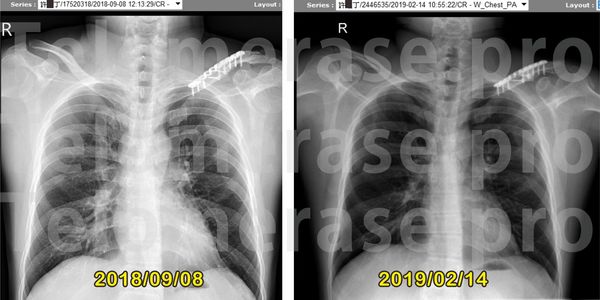

1.肺纖維化

1.肺部已恢復正常

5.肺纖維化問題改善很多